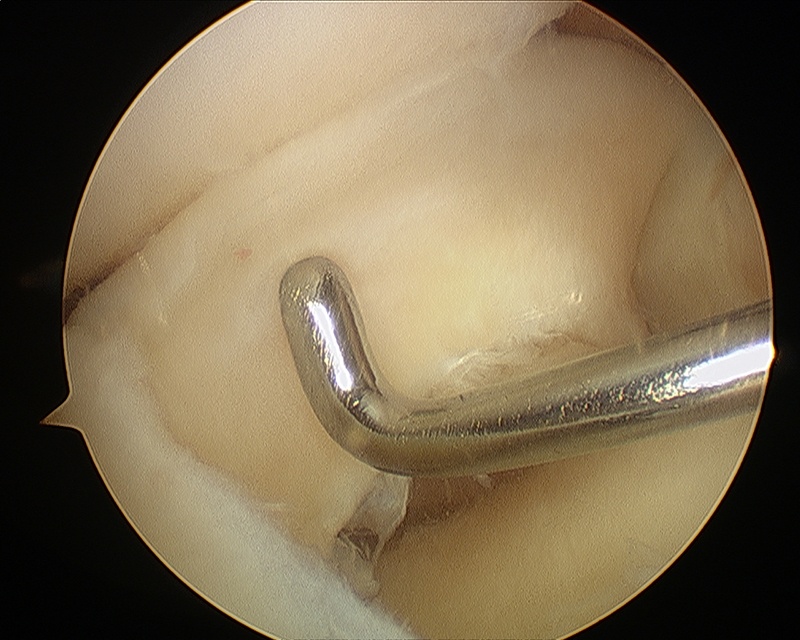

Microfracture

-

Microfracture IFC

Chondral Tibial Flap And Microfracture

Performing Microfracture